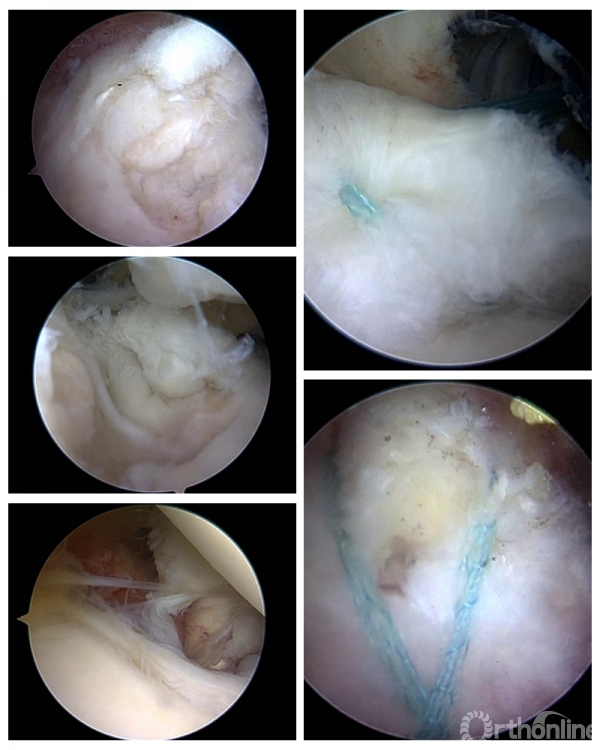

在两天的会议中,成功完成了11台手术,包括4台膝关节韧带重建、2台膝关节内侧骨关节炎单髁置换、1台肩关节前方复发性不稳定改良Bristow稳定术,1台巨大肩袖撕裂SCR修补、1台肩肩胛下肌冈上肌撕裂修补、1台跟腱痛风性腱病伴撕裂清理修补、1台距骨骨囊肿关节镜下清理植骨。

手术病例分享:

△手术名称:左膝前交叉韧带撕裂类等长重建 术者:陈世益教授

△手术名称:肩关节前方复发性不稳定改良Bristow稳定术 术者:崔国庆教授

△手术名称:前后交叉韧带重建 术者:李箭教授、张文涛教授(三台手术)

△手术名称:巨大肩袖撕裂 上关节囊重建 术者:丁少华教授

△手术名称:肩胛下肌、冈上肌撕裂修补 术者:李瑾教授

△手术名称:跟腱痛风性腱病伴撕裂、Haglund畸形清理成形跟腱修补术 术者:华英汇教授